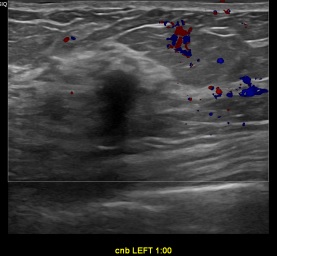

상기환자는 외부검사이상소견으로 내원하신 40대후반

여성분으로 의심스러운 좌측혹 조직검사 시행해 침윤성암으로 진단되었습니다